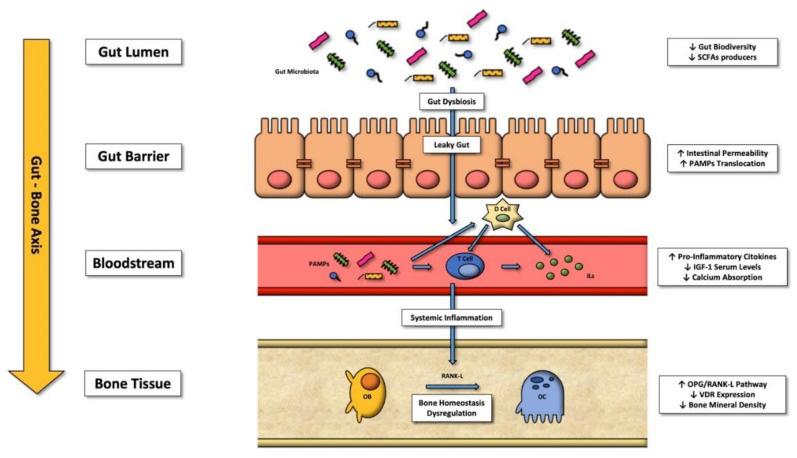

FIGURE 1 The gutbone axis The gut-bone axis: pathways and factors starting from gut dysbiosis that determine bone metabolism alterations favoring osteoclasts. Abbreviations — SCFAs: short-chain fatty acids; PAMPs: pathogenassociated molecular patterns; D Cell: somatostatinproducing cells; T Cell: type of leukocyte that is an essential part of the immune system; OB: osteoblast; OC: osteoclast; RNK-L: receptor activator of nuclear factor-κB ligand; OPG: osteoprotegerin; VDR: vitamin D receptor; IGF-1: insulin-like growth factor one. Taken from: SireA, deSireR, CurciC, CastiglioneF, WahliW. Role of Dietary Supplements and Probiotics in Modulating Microbiotaand Bone Health: The GutBone Axis. Cells.2022Feb21;11(4):743.doi:10.3390/cells11040743.PMID:35203401;PMCID:PMC8870226.

The relationship between gut health and bone health - known as the gut-bone axis - is an emerging area of scientific research8 (Figure 1).

Today, altered intestinal homeostasis is being in vestigated as a potential additional risk factor for reduced bone health, and therefore as a new potential therapeutic target. Intestinal microflora affects osteoclast activity, regulating serum IGF1 levels, and at the same time affects intestinal calcium absorption. It is therefore not surprising that gut dysbiosis affects bone health. In this context, it has been hypothesized that dietary supplements, prebiotics and probiotics contribute to the intestinal microecological balance, which is important for bone health.

There are a number of possible ways in which this can be connected. First, intestinal dysbiosis makes it difficult to absorb calcium in the intestines. In addition, several metabolites produced in the gut exert control over the cells responsible for bone repair. Finally, dysbiosisinduced intestinal permeability causes the release of inflammatory cytokines into the bloodstream, which can negatively affect BMD and other factors related to bone health.

Prebiotics and probiotics have been investigated for their ability to improve bone health through effects on the gut microbiome. Although more research is needed, some evidence suggests that probiotics may protect against BMD loss and may improve markers of bone turnover in postmenopausal women.